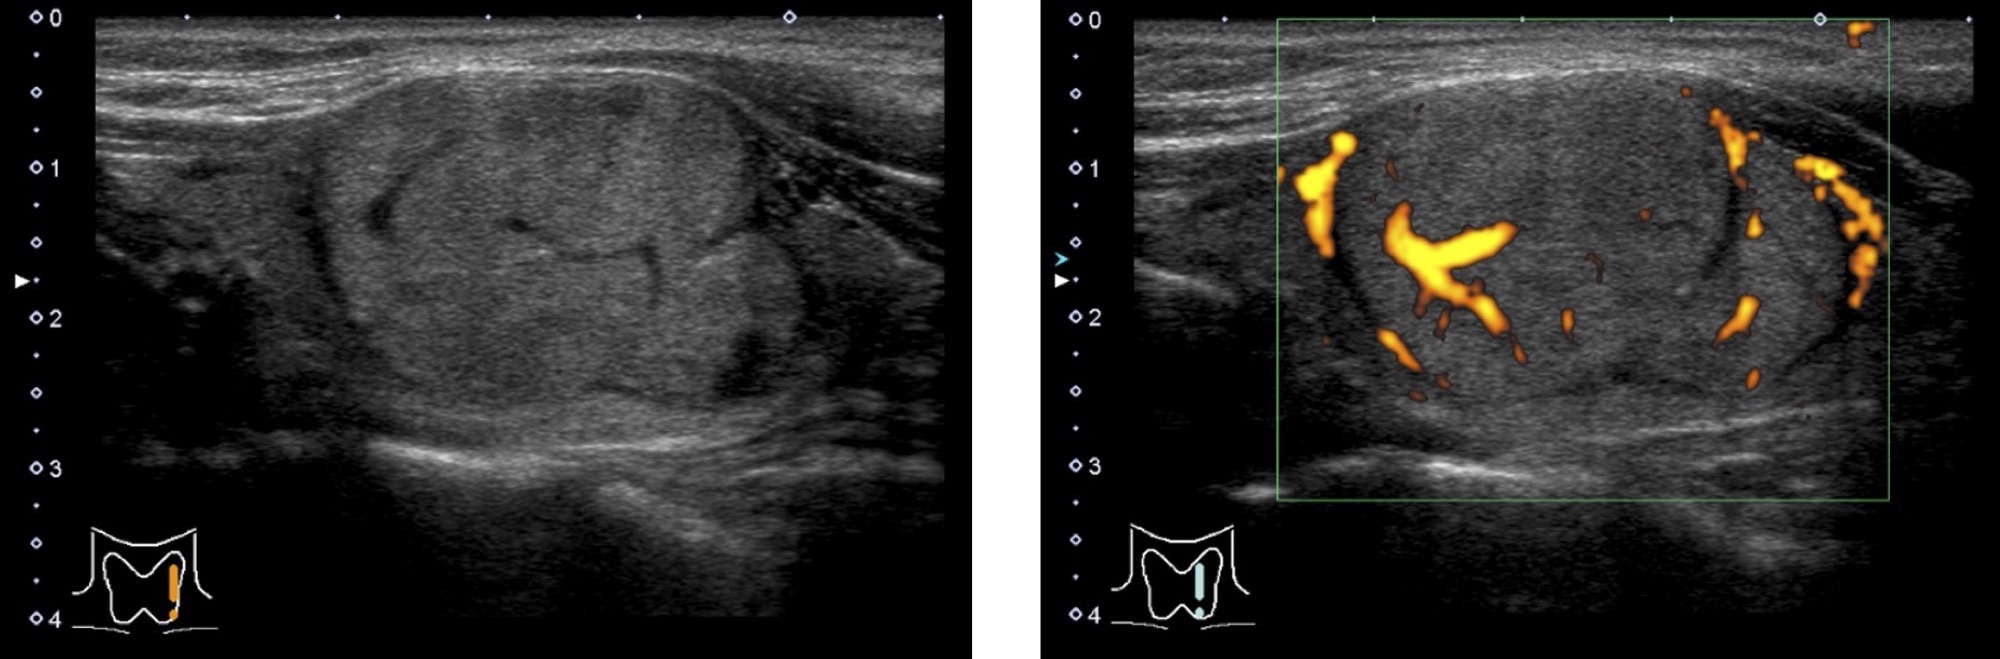

腺腫様結節・腺腫様甲状腺腫

形は円形から楕円形で、甲状腺との境界がはっきりしていることが多いです(境界明瞭)。

内部に嚢胞液(超音波画像では黒く見えます)が含まれている場合も多いですが、ほとんど含まれていない場合もあります。

腺腫様結節は多発することも多く、その場合は腺腫様甲状腺腫と呼ばれます。

濾胞腺腫

形は円形から楕円形で、甲状腺との境界がはっきりしていることが多いです(境界明瞭)。

内部は充実性(固体)のことが多いです。

悪性腫瘍の濾胞がんとは区別が難しい場合が多いです。